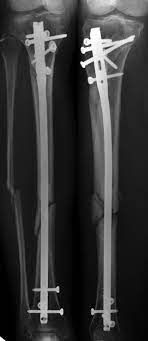

Accident and Trauma Car